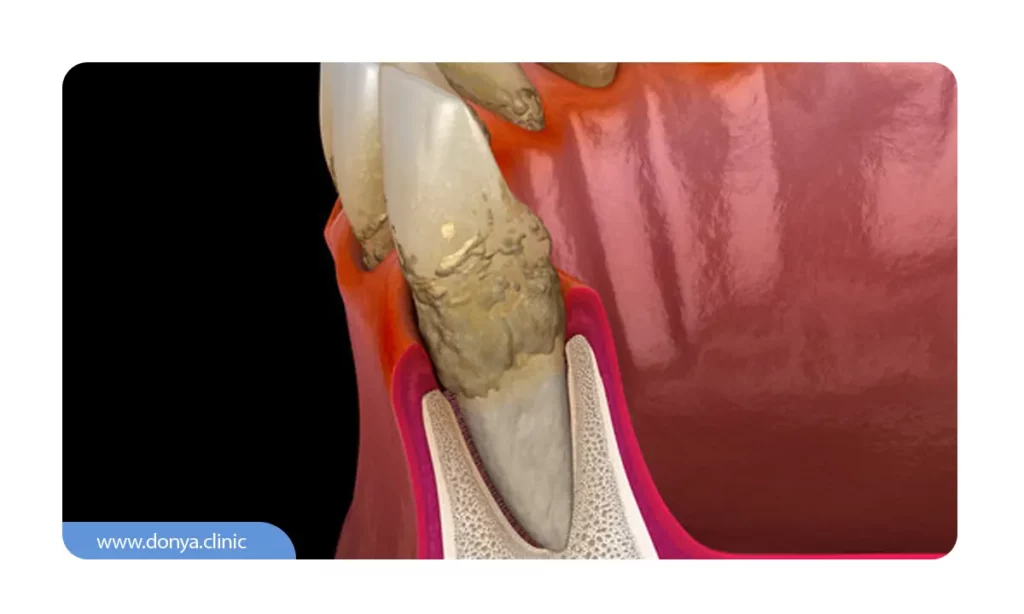

اگر مسواک نزنیم و سایر اصول بهداشتی را رعایت نکنیم کم کم پلاک دندانی سفت و سخت شده و در نهایت تبدیل به جرم سختی به نام تاتار می شود. تارتار علت تحلیل لثه در بسیاری از افراد است. این جرم روی دندان ها سفت شده و به سمت لثه ها حرکت می کند. در نهایت تارتار جرم باعث عقب نشینی لثه می شود.

در صورت عدم بازسازی به زودی جیب های کوچکی (ساختاری که به آن جیب یا پاکت پریودنتال گفته می شود) ایجاد شده و باکتری های بیشتری در آن قرار می گیرند. این می تواند باعث عفونت شده و در نهایت بافت لثه و استخوان را آلوده کند.

تحلیل خفیف لثه احتمالا توسط دندانپزشک و با روش هایی مانند جرم گیری دندان از بین می رود و خود به خود ترمیم می شود. در طی جرم گیری که به آن فرآیند اسکیلینگ و روت پلنینگ گفته می شود. پلاک، تارتار و جرم دندانی که به زیر خط لثه رسیده از بین برده می شوند. همچنین برای از بین بردن سایر باکتری ها و عفونت های باقی مانده آنتی بیوتیک تزریق می شود. اما اگر رکود لثه به قدری زیاد باشد که به استخوان و دندان آسیب رسیده باشد با جرم گیری دندان نمی توان مشکل را برطرف کرد و باید برای ترمیم ساختارهای آسیب دیده مداخلات دندانپزشکی بیشتری در نظر گرفت.

- پوسیدگی ریشه دندان: با نمایان شدن ریشه دندان، احتمال پوسیدگی آن افزایش می یابد.